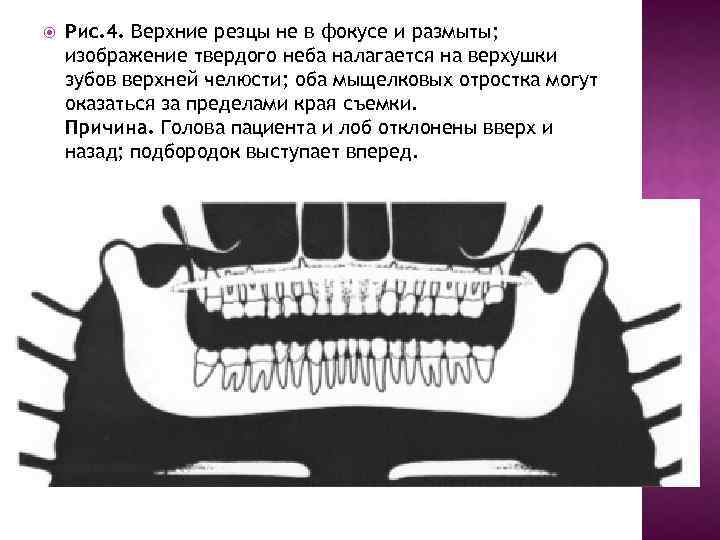

Рис. 4. Верхние резцы не в фокусе и размыты; изображение твердого неба налагается на верхушки зубов верхней челюсти; оба мыщелковых отростка могут оказаться за пределами края съемки. Причина. Голова пациента и лоб отклонены вверх и назад; подбородок выступает вперед.